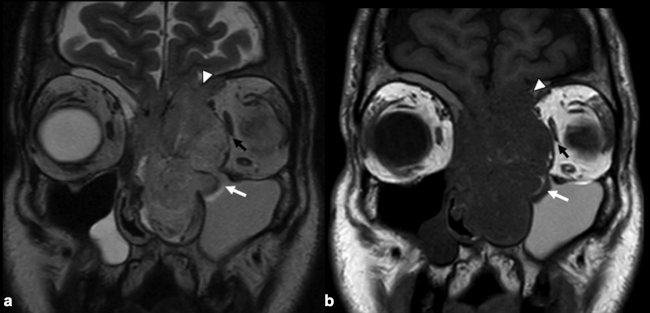

La RM es la prueba de imagen de elección para evaluar los detalles de la extensión y la estadificación locorregional del tumor. La RM es superior a la TC para determinar el grado de afectación del tejido blando (►Fig. 9) con una mejor evaluación de la afectación intracraneal (►Figs.10,11,12,13,14), orbital (►Figs.14y15), de la base del cráneo y la invasión perineural.53,54 La RM tiene un valor añadido para distinguir la afectación dural de la del parénquima cerebral (►Fig. 12).55 En la RM, el NBO aparece hipointenso respecto a la sustancia gris en imágenes ponderadas en T1 y de isointenso a hiperintenso en las imágenes ponderadas en T2 (►Figs.10,11,12,13,14,15).56 Muestra un realce homogéneo, excepto en áreas con hemorragia o necrosis. Además, permite diferenciar las secreciones retenidas del tumor, al ser estas hiperintensas ponderadas en T2.53,55 Los hallazgos de imágenes clásicos incluyen una masa “en forma de mancuerna” que se extiende a través de la placa cribiforme (►Fig. 12), con la parte estrecha a nivel de la placa. Los quistes tumorales periféricos (►Figs.5b,12,14,16) y las calcificaciones moteadas son bastante característicos de NBO.1

Las secuencias de RM con saturación de la grasa ayudan a diferenciar el tumor de la grasa orbital y los músculos. Un margen suave de la interfaz tumor-grasa sugiere que la lesión está contenida en la fascia periorbital (►Fig. 15), mientras que un margen irregular favorece la invasión franca de la órbita.35,49,57 Sin embargo, el diagnóstico definitivo de invasión de la duramadre y los tejidos periorbitarios solo es posible en la cirugía.49